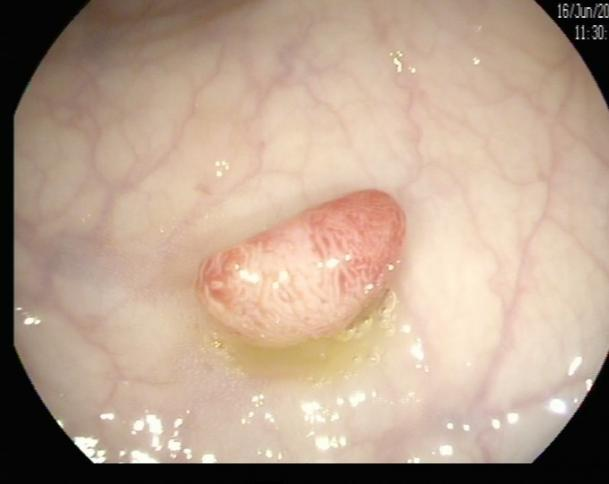

邓先生(54岁,乙状结肠息肉,图3)

肠镜一照,息肉现形!形态各异的大肠息肉,离癌有多远?(图3)

图3

病理诊断:(乙状结肠)管状腺瘤。

解读:这是最常见的腺瘤类型。若未发现高级别瘤变或癌变,属于相对早期的癌前病变。但放任不管,其癌变风险随时间推移而增加。距离癌:潜在风险,癌前病变早期。